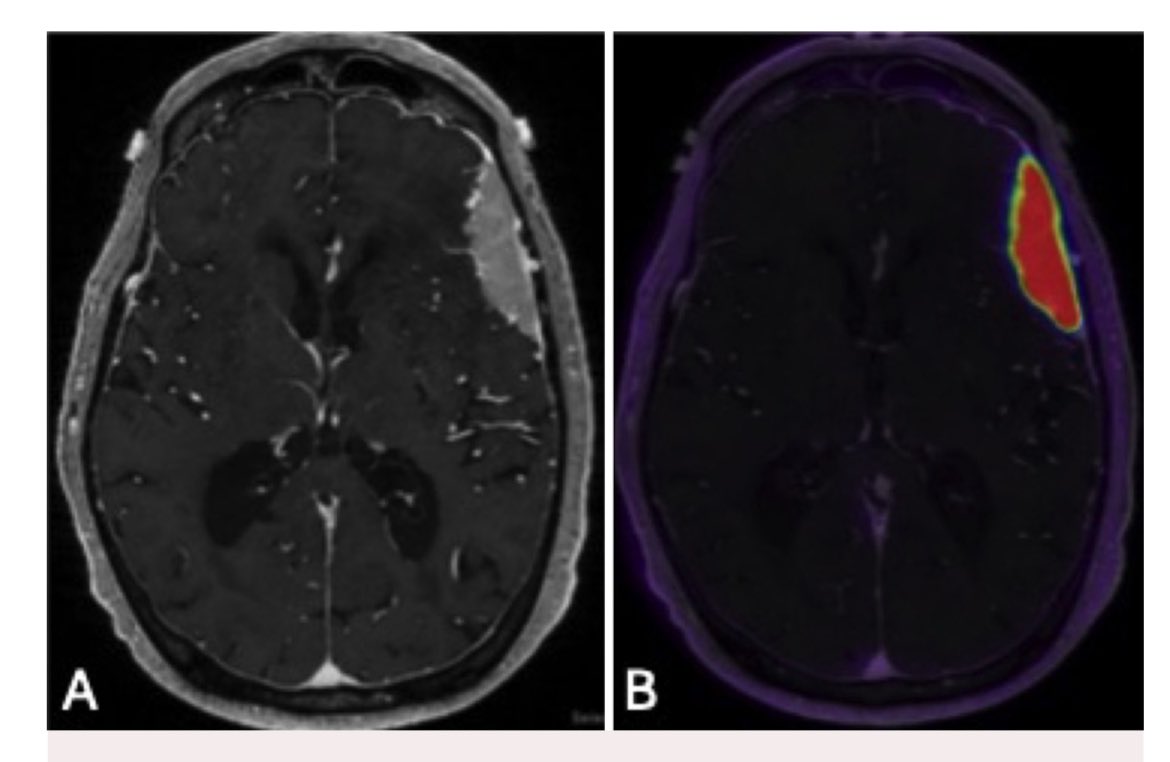

Clinical #brain #PET exams #neurorad fellow extraordinaire @MarcusKonner & I read @WCMRadiology @MolecularWCM this week: -FDG: AD vs FTD -Florbetaben: ?AD -Flortaucipir: AD staging -FDOPA: ?DLB -FLUCICLOVINE: GBM PD vs RN -DOTATATE: meningioma PD vs RN #thefutureisnow @TheASNR